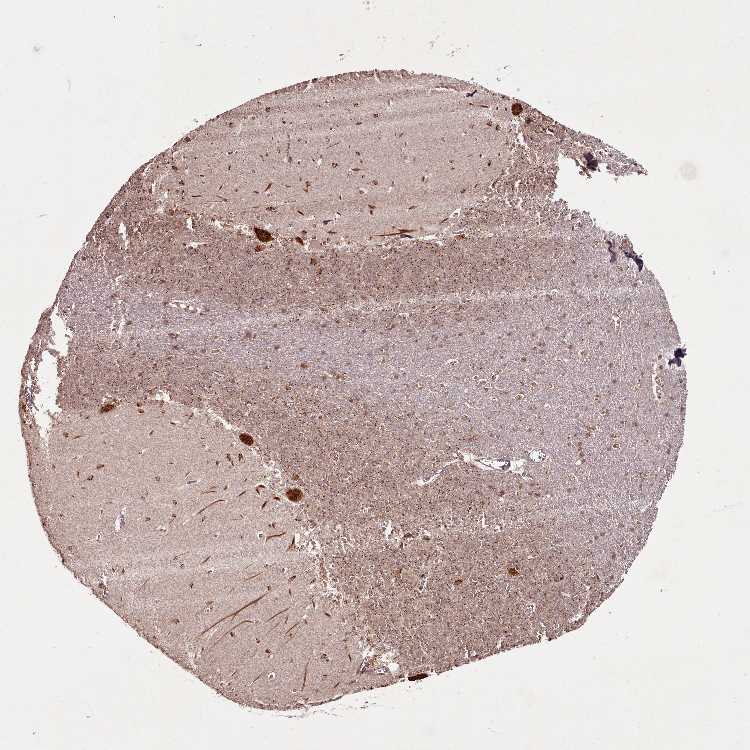

CEREBELLUM - Antibody stainingi

Antibody staining in the annotated cell types in the current human tissue is reported as not detected, low, medium, or high, based on conventional immunohistochemistry profiling in selected tissues. This score is based on the combination of the staining intensity and fraction of stained cells.

Each image is clickable and will lead to virtual microscopy that enables deeper exploration of all samples and also displays staining intensity scores, fraction scores and subcellular localization as well as patient and tissue information for each sample.

Antibody HPA038161

Purkinje cells High

Cells in granular layer Medium

Cells in molecular layer High